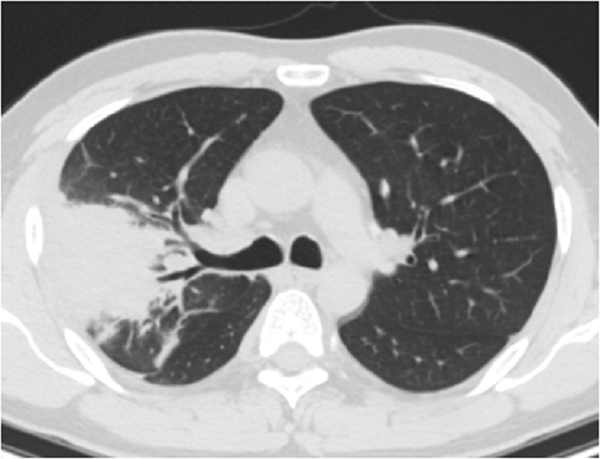

![甲状腺癌の肺転移と鑑別を要する肺の病気[日本甲状腺学会認定 甲状腺専門医 橋本病 バセドウ病 甲状腺超音波エコー検査 長崎甲状腺クリニック(大阪)]](https://www.nagasaki-clinic.com/images/special/thyroid11/images20200701222927.jpg)